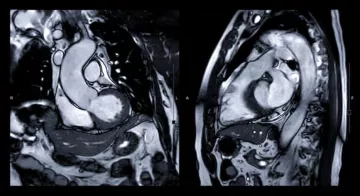

Première ablation des troubles du rythme guidée par IRM.

Ablation des troubles du rythme guidée par IRM : une première en France

le 20/09/2021 Médecine - Chirurgie - Obstétrique

L’Hôpital privé Jacques Cartier, situé à Massy (91), a procédé à cette première il y a quelques semaines, au sein de l’Institut cardiovasculaire Paris Sud (ICPS).